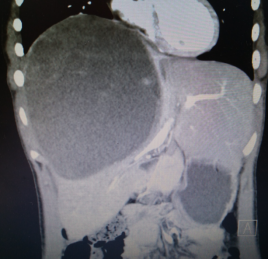

来自四川宜宾的13岁女孩乐乐(化名),体重60斤,去年7月中旬在当地医院检查发现肝内巨大肿瘤。

由于肿瘤巨大,压迫肝脏主要血管并侵犯膈肌,辗转多家医院都被告知,进行手术切除治疗风险巨大。

在经过周密手术准备和规划后,由肝胆外科主任赖钊指导,副主任医师陈杰主刀,副主任医师赵斌担任一助,历时四小时完成肝脏肿瘤切除手术。切除的肿瘤重达近4斤,手术中出血却不到200ml。

术后病检提示该肿瘤为肝母细胞瘤,这是自贡市第四人民医院肝胆外科成立以来所切除的第一例肝母细胞瘤。